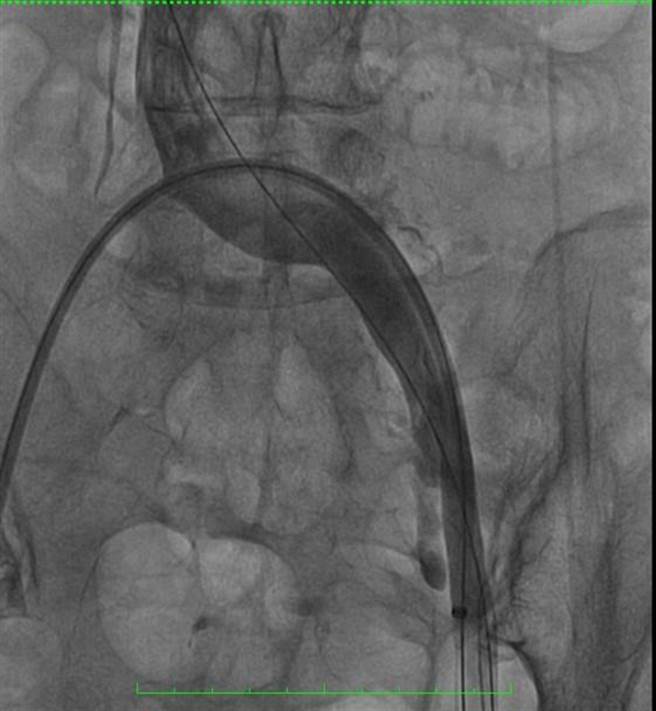

徐中和指出,患者血栓指数(D-dimer)高达2118ng/mL(正常值小于500),于住院期间顺利接受胆结石手术治疗后,及导管溶栓治疗,血管摄影发现左侧髂静脉以及左股静脉大范围血栓,经过Aspirex机械性静脉血栓抽吸导管将血栓顺利取出后,血管摄影发现左侧髂静脉以及左股静脉血流通畅,之后服用新型口服抗凝血剂,逐渐恢復健康。